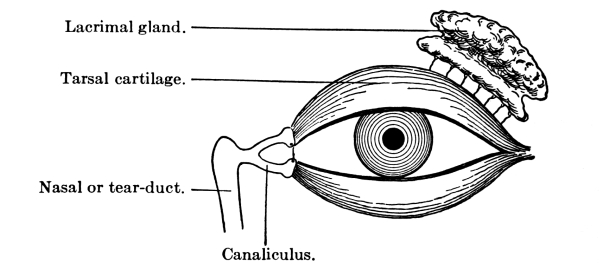

The Nose, 57—The Sense of Smell, 58—The Mouth, 59—The Hyoid Bone, 60—The Teeth, 60—The Sense of Taste, 61—Salivary Glands, 61—The Tonsils, 62—The Ear, 63—Eustachian Tubes, 63—Sensation of Hearing, 65—The Eye, 66—Lachrymal Gland, 68—Coats of the Eye, 68—Light Rays and Sight, 70—Accommodation, 72—Color Perception, 73. |